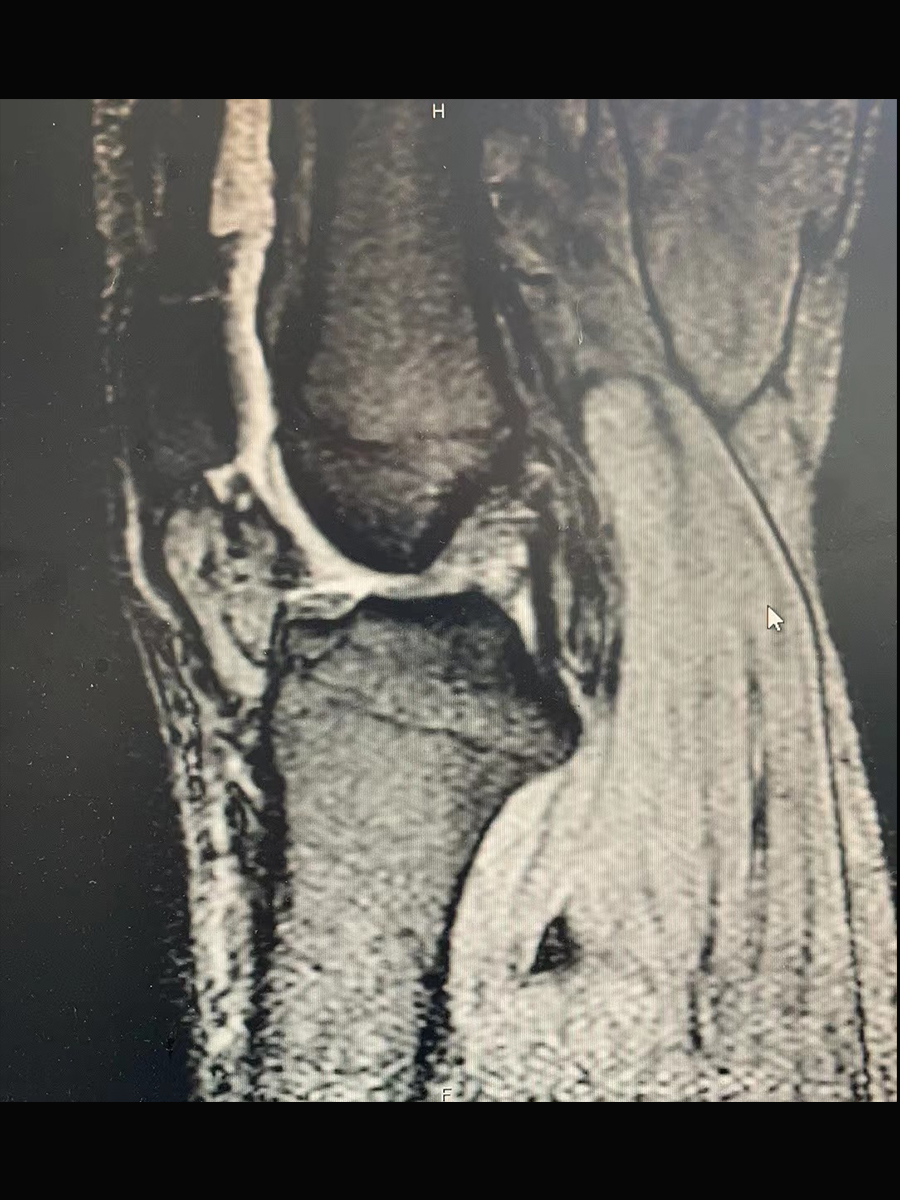

摘要:患者为33岁男性,在篮球运动过程中与他人发生撞击,导致膝关节扭伤,引起膝关节肿胀、疼痛等表现,就诊后通过核磁共振检查,确诊为前十字韧带断裂。建议住院治疗,经过关节镜下前十字韧带重建手术,以及康复锻炼,膝关节疼痛、肿胀缓解,灵活性和功能明显改善。

患者自述喜欢运动,每周定时参加小区内的篮球比赛,在比赛中和别人撞了一下,感觉膝盖扭了,随后膝关节出现肿胀、疼痛、活动受限,在关节肿胀减轻后出现关节不稳症状。考虑是打篮球时膝关节扭转过度牵拉前十字韧带,导致前十字韧带断裂,通过核磁共振检查确认前十字韧带连续性中断,由此确诊为前十字韧带断裂。就病情与患者及家属进行详细沟通后,同意住院治疗。

患者入院后,首先采用冰敷、关节抬高制动等治疗,待膝关节肿胀减轻后采取关节镜下前十字韧带重建手术,恢复关节功能。如果仅采用保守治疗,无法恢复前十字韧带完整性,关节软骨将过度磨损,使关节退行性改变速度加快,最终将影响膝关节使用寿命。手术过程中确认前十字韧带完全断裂,清理韧带断端,确认好韧带上止点和下止点后制作骨道,并取自体腘绳肌肌腱,经过编织后导入骨道内和关节腔内重建前十字韧带。在关节镜下观察膝关节屈伸活动未出现韧带明显松动,关闭手术切口,使用铰链支具进行固定。患者术后配合康复锻炼,恢复膝关节活动范围和膝关节稳定性。